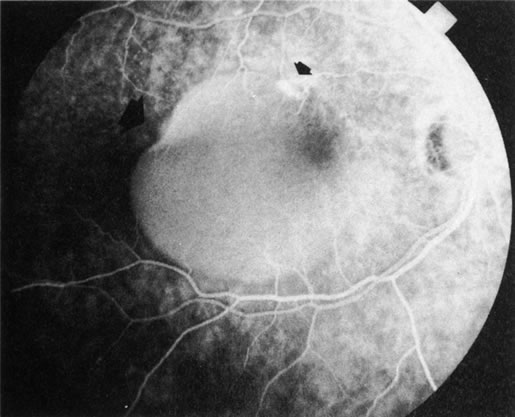

PCV is characterized by the presence of dilated, choroidal vascular channels ending in orange bulging polyp-like dilations in the peripapillary and macular area. Associated features are recurrent subretinal hemorrhage and vitreous hemorrhage, relatively minimal fibrous scarring, absence of retinal vascular disease, pathologic myopia, and signs of intraocular inflammation. FA demonstrates the presence of the dilated vascular channel (Fig. 14 and 15). However, the presence of blood and exudation may block the details of the choroidal circulation on the angiogram. In these cases, ICG angiography can better demonstrate the presence of a distinct network of vessels within the choroid because the larger choroidal vessels are filled with dye.

Fig. 14. A. Color photograph of the right eye shows a ramified pattern of choroidal vascular abnormality irradiating from the peripapillary area toward the macula. The dilated vascular channels end with bulging polyp-like structures. A larger, orange, saccular dilation is seen inferior to the macula (white arrow); leakage of fluid from this vascular abnormality results in serosanguineous pigment epithelium detachment (black arrows). B. The corresponding fluorescein angiogram composite highlights the vascular lesion in the peripapillary area and the serosanguineous detachment of the pigment epithelium that extends inferiorly and temporally off the macula.